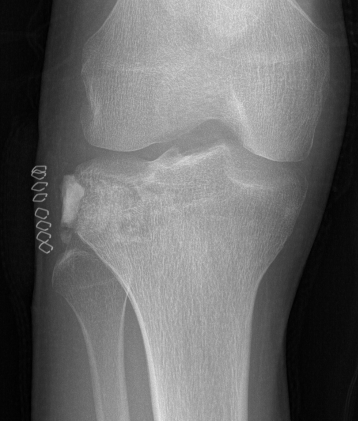

X-ray

Well defined eccentrically located epiphyseal lesion

- thin sclerotic reactive rim

- may have calcification

Evaluate articular surface integrity / compromise

Identify chondroid matrix